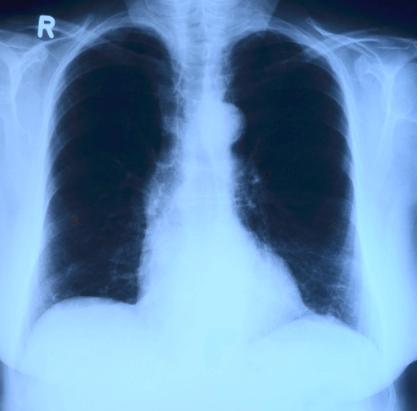

폐암 초기증상에 대해 알아보시나요? 폐암은 3대 암에 들어갈 정도로 많은 사람들이 걸리는 암입니다. 하지만 사망확률이 높은 만큼 조기발견이 가장 중요한데요. 본문에서 폐암이 발생했을 때 나타날 수 있는 초기증상 10가지에 대해 알아보겠습니다.

폐암의 원인은 여러가지가 있겠지만, 가장 큰 원인으로 꼽히는 것은 흡연입니다. 비흡연자에 비해 흡연자는 폐암에 걸릴 확률이 10배 이상 증가하는 것으로 알려져 있는데요. 특히 소세포 폐암의 90% 이상이 흡연과 관련되어 있습니다. 또 다른 원인으로는 대기오염, 유전적 요인, 등이 있습니다.

폐암 초기증상 10가지